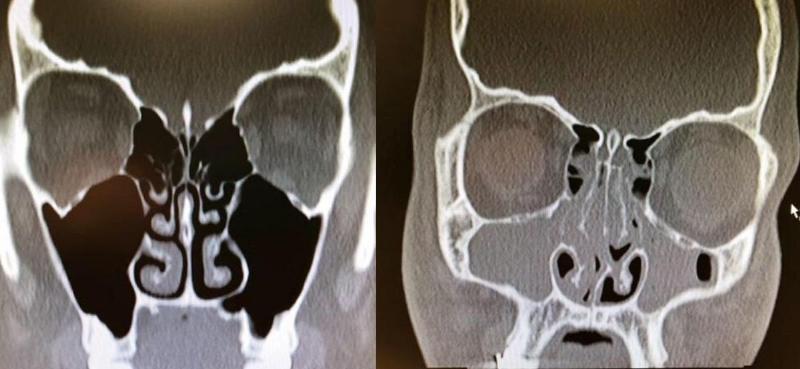

X-Rays of Congested and Un-congested Sinuses Will Make You Grateful for Air

congested and uncongested xray

This is really wild. This person had bad congestion and allergies, so their sinuses were completely swelled up. If this doesn't make you breathe a little easier, then I don't know what will because I'm feeling thankful for my un-congested sinuses, right now.